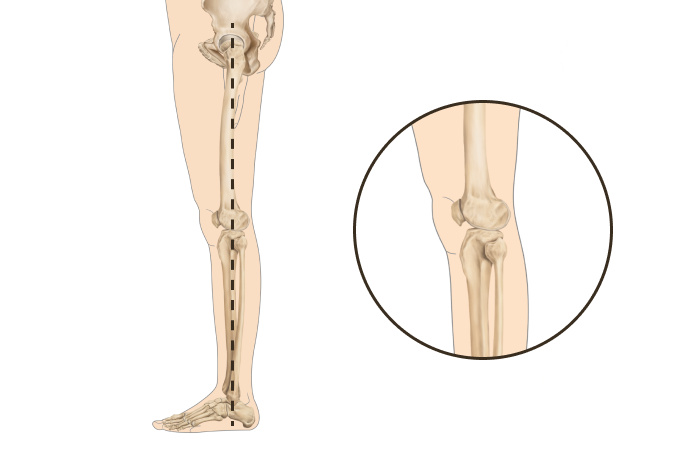

휜다리는 단순히 무릎 사이 간격이 벌어진 것이 아닙니다.

무릎 위의 대퇴골과 아래의 정강이뼈가 회전하면서 무릎까지 뒤로 빠지기 때문에 다리사이 간격이 넓어지는 겁니다.

당당 휜다리

발(아치)-발목-무릎관절-고관절-골반의 서로 다른 회전을 바로 잡는 기술입니다.

• 무릎이 외측으로 벌어지면서 다리 축이 변형됨

• 체중부하가 다리 안쪽(내측)에 집중되어 내측 관절의 압력증가로

무릎관절의 퇴행성 변화와 통증을 초래

• 무릎이 안쪽으로 모이면서 다리 축이 변형됨

• 체중 부하가 다리 바깥쪽에 집중되어 외측 관절의 압력증가로

무릎 통증, 불안정성, 관절 손상을 유발할 수 있음